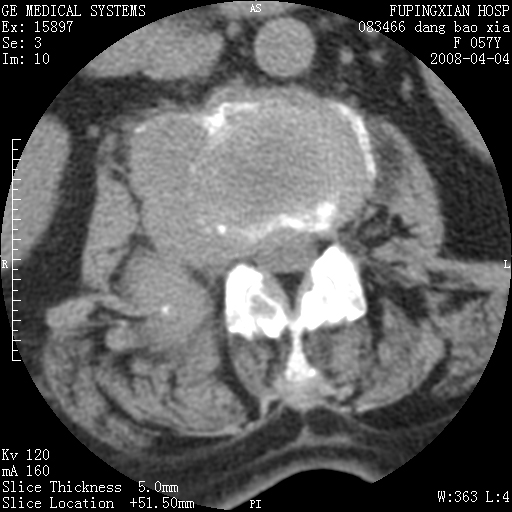

标题: CT12677:女性,57岁,疼痛数月。 [打印本页]

标题: CT12677:女性,57岁,疼痛数月。

椎体及附件骨质破坏同时伴软组织肿块,首先考虑恶性肿瘤。

椎体及附件骨质破坏,伴软组织肿块,首先考虑恶性骨肿瘤,建议提供正侧位片。

骨组织起源,膨胀,软组织肿块=恶性改变:首选骨巨,其次转移瘤,再次脊索瘤

椎体及附件溶骨性破坏,周围巨大软组织肿块,首先考虑转移瘤。